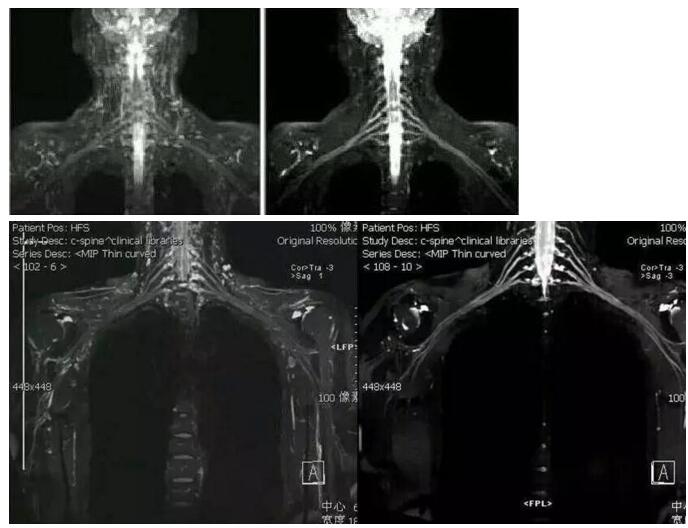

左图为改进前的图像,右图为新技术的图像

由我院医学影像中心经过多次讨论出来的新方案做出来的新图像,相比之前的技术,新方案的图像几乎没有受到的背景信号干扰。

磁共振成像新技术做出来的图像可清晰地显示臂丛神经全貌及周围组织结构关系,能显示神经根的撕裂,还能同时显示合并存在的脊膜膨出、脑脊液外漏、脊髓出血、水肿等。

而且 磁共振水成像技术对显示蛛网膜下隙及脑脊液的外漏更为清楚。在臂丛神经病变的诊断中起有不可磨灭的作用。

根据检查所作图像重建的三维图像,我们可以从各个方位观察臂丛神经